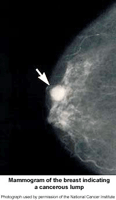

A mammogram is an X-ray image of your breast. It's used to find and diagnose breast disease. A mammogram may be done if you have breast problems such as a lump, pain, or nipple discharge. A mammogram is also done as a screening test if you don’t have breast problems. It can check for breast cancers, noncancerous or benign tumors, and cysts before they can be felt.

A mammogram can’t prove that an abnormal area is cancer. If a mammogram shows an area in your breast that is abnormal or may be cancer, follow up tests such as a breast ultrasound exam or an MRI may be done. For a conclusive diagnosis your healthcare provider removes a sample of breast tissue (biopsy) by needle or during surgery. The tissue will be examined at a lab under a microscope to see if it's cancer.